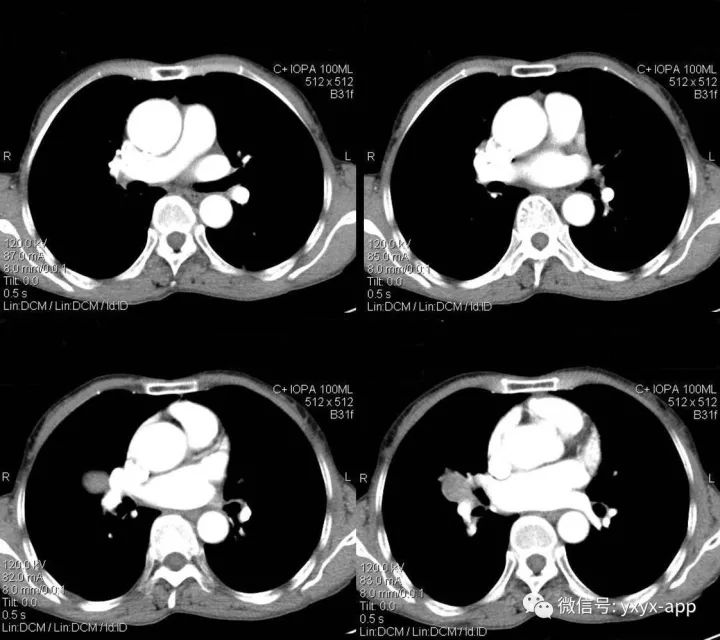

肚肚丫头:右肺门结节影,边界清,密度尚均匀,增强扫描动脉期,病变呈轻度强化,静脉期强化明显(与血管相当),病灶部分与支气管相贴。纵隔未见肿大的淋巴结。考虑与血管相关的良性病变可能。1.硬化性血管瘤;2. 巨淋巴结增生不除外

2.CT平扫病灶密度较均匀,与肌肉密度相近,多数PSH增强扫描动脉期有所强化,静脉期及延迟期持续均匀强化;少数为不均匀强化。较小病灶以血管瘤型和乳头型为主,强化较明显且均匀;随着病灶增大,实体型和硬化型成分逐渐增多,强化程度随之减低且不均匀。

3.相对特殊征象有①空气新月征:少数PSH表现为病灶边缘新月形或半月形无肺纹理区;②贴边血管征:表现为边缘明显强化的点状血管断面,动脉期强化明显且先于病灶本身强化,与肺动脉强化程度相近;③尾征:表现为瘤边缘尾状突起且多位于病灶近端靠近肺门一侧。

本例特点为①病灶为圆形,小于3cm,边缘光滑,无钙化及囊变;②肿瘤增强扫描为动脉期有所强化,静脉期持续均匀强化,与同层肺动脉相近;③相对特殊征象:仅见动脉期贴边血管征,未见空气新月征及尾征。本例主要要与肺无脂肪和钙化的错构瘤鉴别,以及炎性肌纤维母细胞瘤鉴别,后两者均不具有持续均匀强化的特点,可做鉴别。而巨淋巴结增生症动脉期明显强化,静脉期回落,与本例强化时相不符。